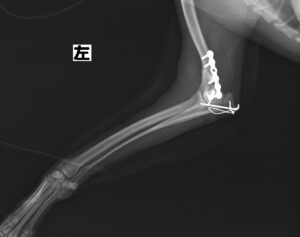

階段からころげおちてかかりつけ医を受診し、X線にて左側「上腕骨外顆骨折」を認めたため、当院の整形外科にご紹介いただきました。この症例は、尺骨の骨切り術を併用し外顆の骨折部分を整復しています。術後の経過は良好で、手術から7ヶ月後に尺骨のインプラントを除去し、治療終了としました。